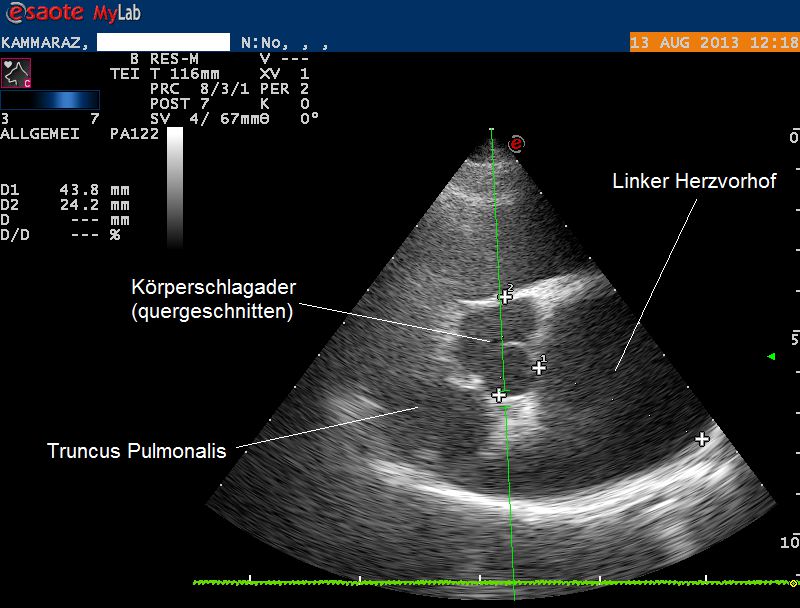

Der Herzultraschall bestätigt den röntgenologischen Verdacht eines Herzproblems: Sowohl die Hauptkammer als auch der linke Vorhof sind bei Karammaz stark erweitert; die Kammer zieht sich ausserdem in der Pumpphase des Herzen zu wenig zusammen, wodurch das Organ zuwenig Blut fördern kann. Im Doppler-Ultraschall ist zu erkennen, dass durch die Erweiterung des Herzen auch die Klappen zwischen linkem Vorhof und linker Kammer undicht geworden sind und Blut beim Pumpen zum Teil nicht in den Körper, sondern zurück in den Vorhof gepumpt wird. Sonografisch ist also ein typisches Bild einer sogenannten Dilatativen Cardiomyopathie (DCM, Herzmuskelerkrankung, welche mit einer Erweiterung einhergeht) vorhanden; als Folge der geringen Pumpleistung des Herzen hat sich ausserdem ein Lungenödem gebildet.